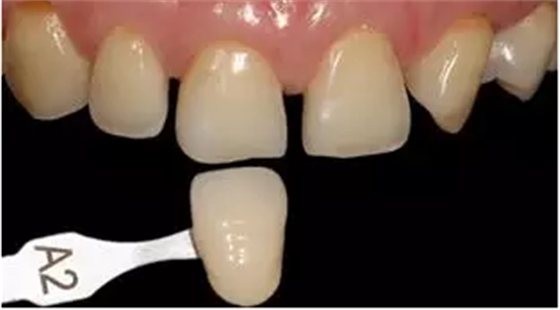

4.比色:自然光源、牙面濕潤情況下進(jìn)行比色,使用比色板(義獲嘉,列支敦士登)5s 內(nèi)確定顏色為 A2,根據(jù)瓷納美樹脂(登士柏,美國)配色板,牙本質(zhì)色選擇 D2,牙釉質(zhì)色選擇 E2。

比色板 術(shù)前比色,A2色

瓷納美樹脂配色板 瓷納美樹脂